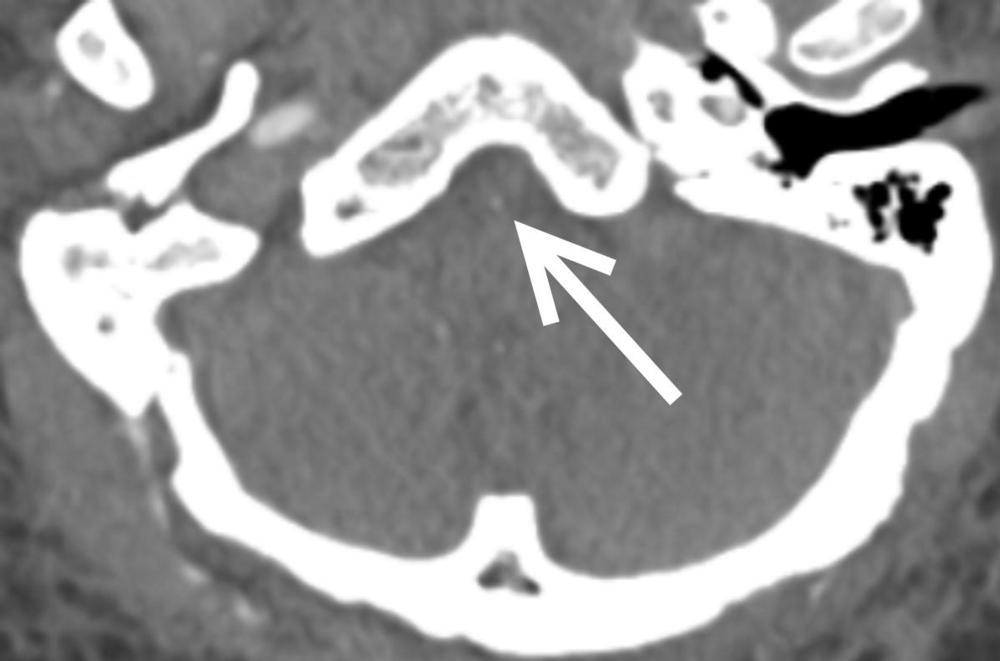

Figure 2. CT of the brain blood vessels of a SARS-CoV-2-positive patient shows a nearly blocked basilar artery (arrow) next to the brain stem. The patient needed an emergency procedure to open the artery.

High-res (TIF) version

Figure 3. CT of the brain’s blood vessels shows a nearly blocked artery next to the brain stem. The patient needed an emergency procedure to open the artery.

Figure 4. CT of the brain’s blood vessels shows a nearly blocked artery next to the brain stem (arrow). The patient needed an emergency procedure to open the artery.